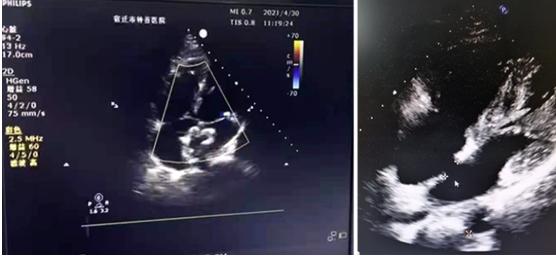

△术前彩超

患者刘某,因体检发现存在“先天性心脏病——房间隔缺损”后至宿迁市钟吾医院心血管内科门诊就诊,心脏彩超显示其房间隔缺损约15mm,我院心血管内科主任程春齐接诊患者后,积极与患者及其家属沟通病情,并向他们详细介绍了目前最佳的治疗方案为行“房间隔介入封堵术”。